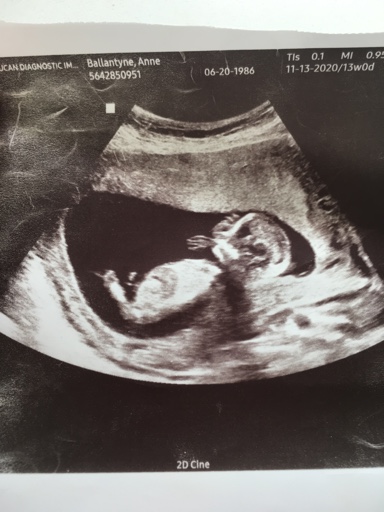

13 week ultrasound pics

Attachment 43309